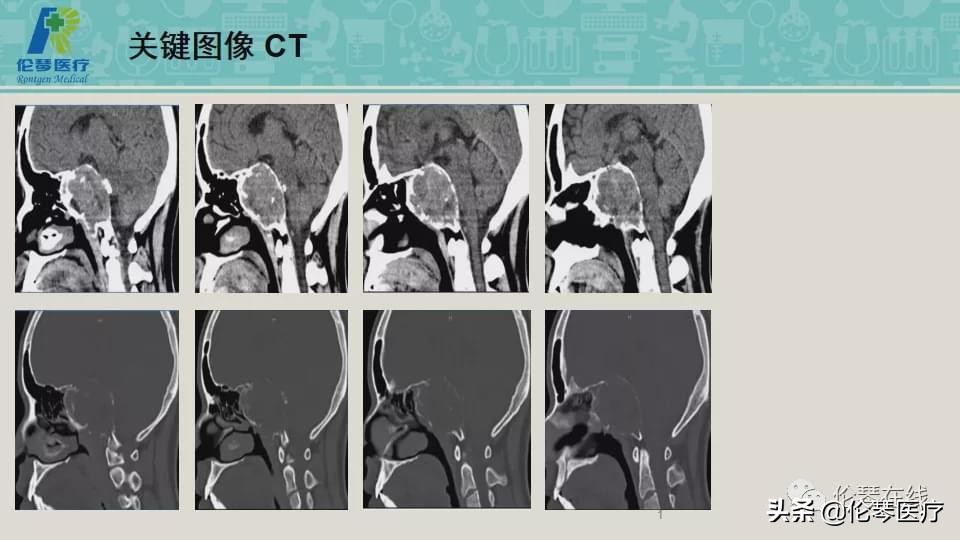

性别:男

年龄:21岁

主诉:头痛,双眼内收、外展受限8个月,加重2月

检查:CT扫描(影像图像见下方)